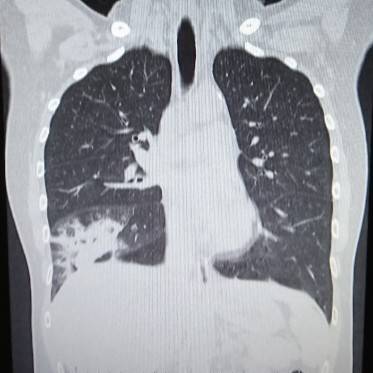

CTの写真を何枚か見てみましょう。

これならわかる。

CTは肺炎を見つけるのが得意です。

イガイガと汚く見えるところが肺炎です。

撮影した時点では肺炎かどうかはわからないので、放射線科内でも「ココが汚い」という表現をよくします。

もう一度、先程のCTを見てみると汚い部分がくっきりと限局しているのがわかります。

このような肺炎を区域性肺炎といいます。

肺がんの場合は浸潤していくので肺の区域に関係なく大きくなっていきます。

気管支透亮像

こちらも肺炎に特徴的な所見です。

air bronchogram(えあーぶろんこぐらむ)とも言います。

先程の患者さんにも見られますが、もっとわかりやすいのがコチラです。

同じように区域性ですが、左右両肺とも広い範囲で炎症を起こしています。

そして炎症の中に気管支が透けて見えています。

これが気管支透亮像です。

肺がんの場合は気管支にもどんどん浸潤していくので気管支は途絶してしまいます。